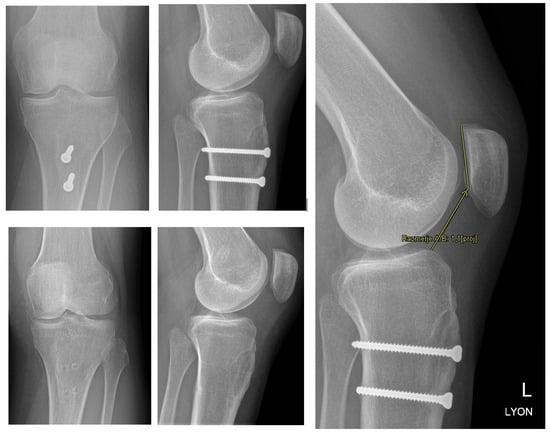

Medial Patellofemoral Ligament and Lateral Patellofemoral Ligament Reconstruction after Tibial Tuberosity Transposition in a Young Woman with Patellar Instability

- Servien, E.; Verdonk, P.C.; Neyret, P. Tibial Tuberosity Transfer for Episodic Patellar Dislocation. Sports Med. Arthrosc. 2007, 15, 61–67. [Google Scholar] [CrossRef]